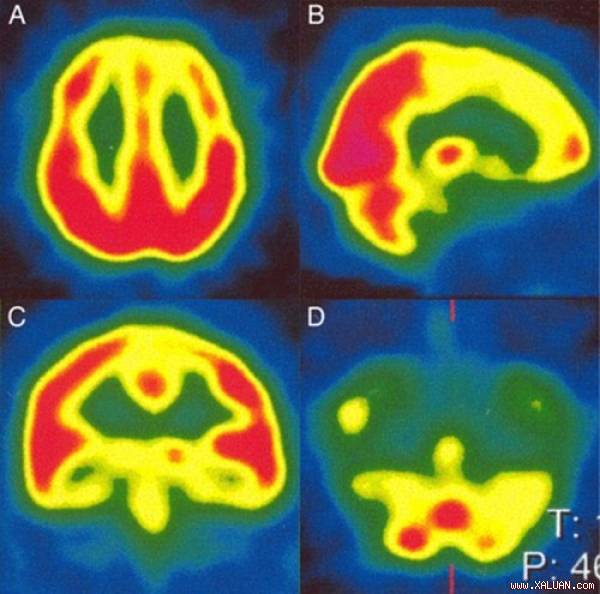

Vùng não chịu trách nhiệm cho ghi nhớ và học tập của bệnh nhân bị tổn thương.

Các bác sỹ đã tiến hành chụp cộng hưởng từ MRI để tìm ra nguyên nhân của chứng bệnh kỳ lạ này. Máy quét cho thấy, khu vực não chịu trách nhiệm cho bộ nhớ và học tập đã bị thiệt hại.

Họ cho biết, đây là tác dụng phụ hiếm có gây ra bởi sự gián đoạn trong dòng chảy của máu đến não trong quá trình phẫu thuật. Có thể lượng máu đã hạn chế chảy trong hoặc ngay khi đang phẫu thuật.

“Việc tuần hoàn máu kém khiến cho não trước thiếu oxy và chất dinh dưỡng. Kế quả là chức năng não bị tổn thương.”. Tiến sỹ Fabio, nhà thần kinh học tại bệnh viện Tây Toronto, Canada cho hay.